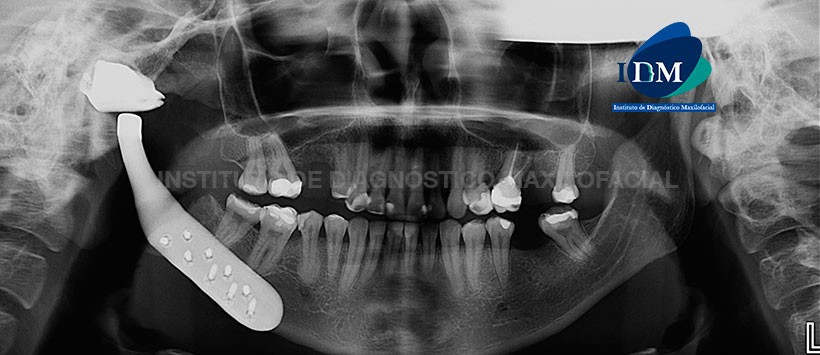

Paciente de sexo femenino de 30 años de edad, acude al Instituto de Diagnóstico Maxilofacial para un estudio imagenólogico de control después de someterse a una cirugía temporomandibular de lado derecho.

A la evaluación de la radiografía panorámica, se pudo observar la neumatización alveolar de ambos senos maxilares. Múltiples restauraciones y ausencias de piezas dentarias así como la presencia de material de obturación en la pieza 26. Siendo lo mas resaltante la presencia de una imagen radiopaca localizada en cuerpo, rama, condio y eminacia articular de lado derecho, constitutida de densidad metálica. Asi mismo se evidencio la presencia de 9 tornillos de fijación en cuerpo mandibular de lado derecho. (Figura 1)